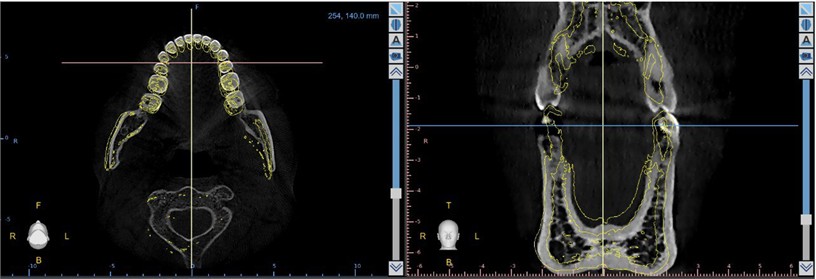

The appliance generated remodeling on maxillae and mandible even without mechanical forces (Fig. 3). The presence of the acrylic touching the palate generated remodeling on transversal direction. Each fifteen days the acrylic was adjusted together with the Coffin. The tongue pressure on Coffin also act as a stimulus to enhance palatal transversal remodeling.

Fig. 3CBCT 3D reconstruction showing the effect of the therapeutic. Merged image shows the high level of remodeling on right side

The remodeling of the basal and alveolar bone caused a passive teeth movement allowing the correction of malocclusion (Fig. 4). Inferior arch also suffered remodeling, equilibrating the transversal dimension (Fig. 5).

Fig. 5Inferior arch remodeling. Yellow lines show the initial shape of the inferior arch and the original position of the teeth